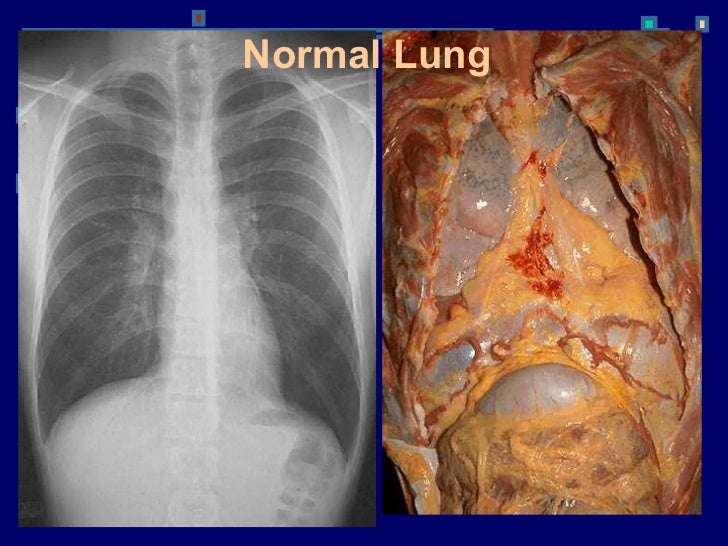

РЕЦИДИВ РАКА ЛЕГКИХ

Опасное заболевание — онкология легких. Это недуг поражает все больше людей. Больных, которым поставлен этот диагноз, волнует вопрос: сколько живут с раком легких. На данной стадии опухоль стремительно разрастается, образуя метастазирование в соседние структуры: печень, желудок, кишечник и другие жизненно важные органы. У таких больных шансов на выздоровление практически не имеется. Поэтому важно вовремя обращаться к врачу за помощью, обследованием и лечением.

· Рецидив рака легкого – повторное развитие злокачественной опухоли после хирургического лечения, химиотерапии или лучевой терапии первичного новообразования. Может поражать ткань легких и бронхов, средостение и 5/5(3). Согласно статистике, рецидив рака легких возникает у % пациентов с первичной резектабельной опухолью. Максимальное количество случаев рецидивов случается в первые 10 месяцев после окончания курса лечения. Рецидив рака лёгких. При раке лёгкого поражаются клетки бронхиальной системы. Его рецидив выявляется за года с момента заключения диагноза. Больные теряют вес и кашляют кровью.